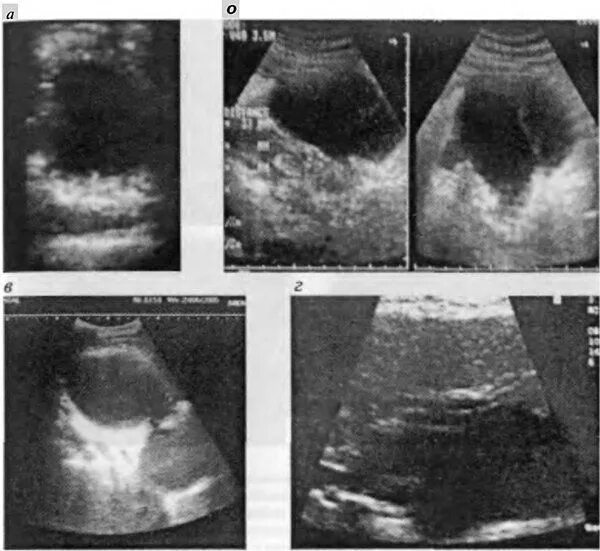

Диффузные изменения киста поджелудочной железы